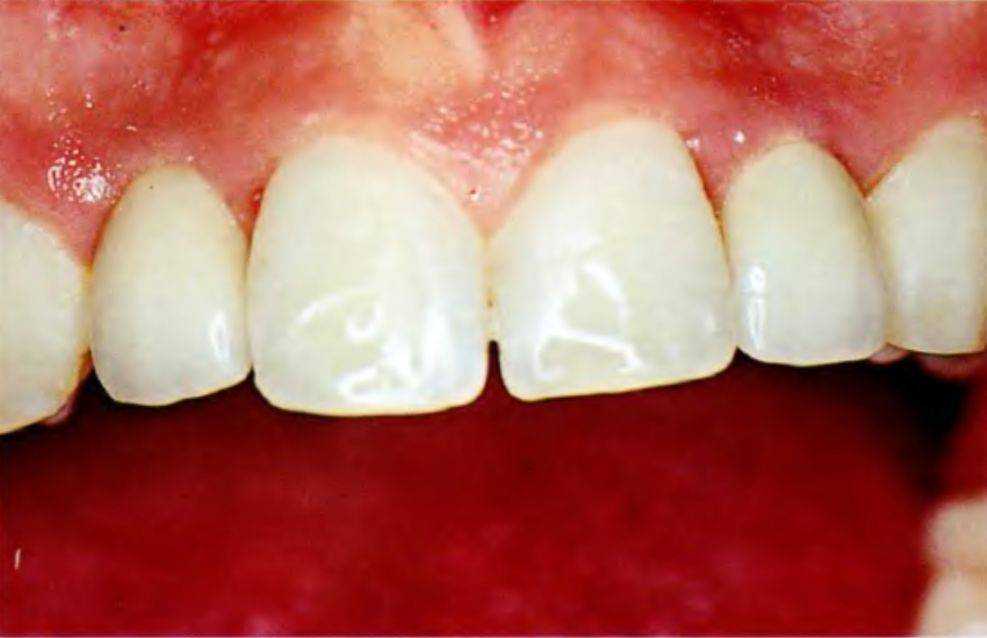

Рис. 5-3z. Цельнокерамические коронки с опорой на имплантаты

После достижения 18 лет пациенту была проведена установка имплантатов в участках адентии, а через 3 мес после этого были фиксированы окончательные реставрации (рис. 5-3z). На рис. 5-Заа представлен окончательный результат лечения, удовлетворивший пациента.